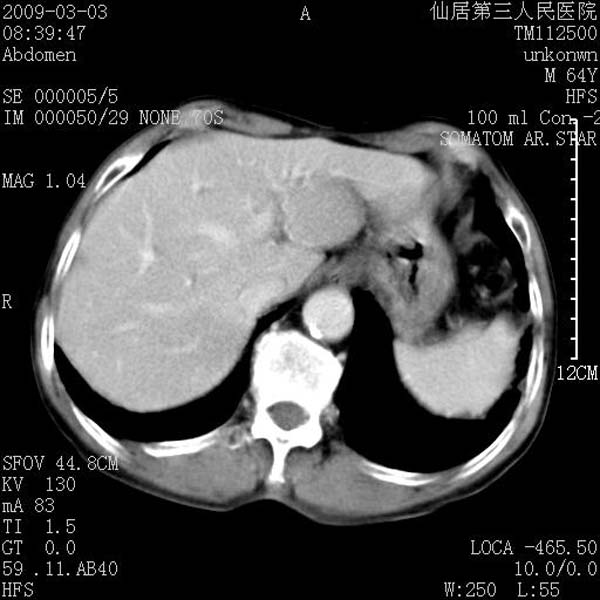

标题: CT18469:男性,64y,体检B超示肝脏低回声肿块,有胃溃疡手术 [打印本页]

标题: CT18469:男性,64y,体检B超示肝脏低回声肿块,有胃溃疡手术

患者,男性,64y,体检b超示肝脏低回声肿块,有胃溃疡手术史。

考虑----胃肠道间质瘤可能性大

从平扫及增强的特点来看,支持肝脏腺瘤并出血。

考虑胃间质瘤可能性大。

胃肠道间质瘤!

ct值呢?感觉没强化,象囊性。

考虑肝静脉韧带裂区良性占位性病变(囊肿?)。

考虑肝囊肿并出血可能性大.

考虑高密度囊肿可能性大